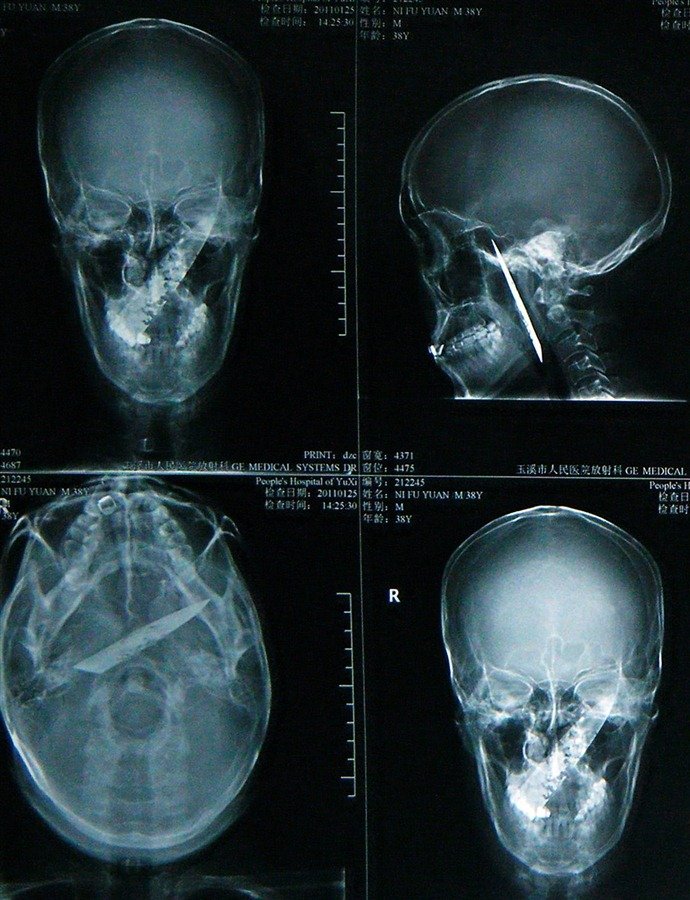

وعرف الطبيب أن المشكلة لم تكن في جهازه الهضمي بل في رأسه أمر الطبيب على الفور بإجراء فحص بالأشعة المقطعية وجاءت النتائج، صادمه جميع الأطباء بما رأوه داخل رأسه، كان عبارة عن شفرة سكين بطول 10 سم غائرة من الخد الأيمن من الجمجمة، والجزء الأكثر إثارة للصدمة هو أن الشفرة كانت بطول 3 سم، وكان السطح متآكل وصدى وكانت على بعد 5 مم من الشريان الخارجي،

وخلص الطبيب إلى أنه من المحتمل أن تكون الشفره داخل رأس فويوان لمدة 3 أو 4 سنوات، ولحسن الحظ، قطعت عدد قليل من الأعصاب الحرجة في رأسه، لذلك عانى من صداع شديد ولكنه تجنب النتائج الأسوأ وتذكر فويوان حادثة السرقه واتضح أن السلاح الذي استخدمه السارق كان خنجر حاد وبسبب القوة انكسر الخنجر وترك النصل مغروس داخل فكه

واثناء هروب فويوان من السارق تحرك النصل الى عمق رأسه واخترق خمسة أو ستة سم وهذا هو السبب في أن الأطباء لم يكتشفوا أي شىء في البداية و بمرور الوقت، بدأت تصدأ وتختلط بالدم، وبدأ الأطباء في عملية الجراحة لإزالة الشفرة وخططوا لجراحة الجمجمة لإزالة الشفرة و بعد أكثر من 10 ساعات من الجراحة المكثفة نجح الأطباء في إزالة الخنجر وتحسنت مشاكل الصداع ورائحة الفم الكريهة بشكل كبير، واستغرق الأمر عدة أشهر حتى استقرت صحته تدريجيًا مما سمح له بالعودة إلى حياته الطبيعية